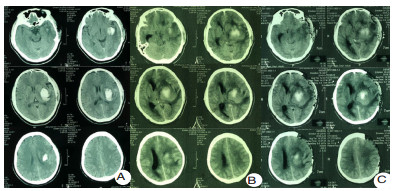

在严重脑损伤的病理生理状态下,尤其是严重的水盐电解质紊乱或感染炎症的状态下,液体的分布将极大的改变全身系统有效血容量,也将影响脑血流灌注而导致影响脑功能。对于神经危重症患者,包括急性中重度颅脑损伤和严重脑卒中患者,急性期需要甘露醇、甘油果糖等脱水渗透性治疗控制颅内压;存在不同程度的感染和全身炎症反应综合征,尤其是严重脓毒血症时,输入的部分液体通过毛细血管的组织间隙渗漏,液体存在异常分布,炎症的严重程度与体液异常分布的程度显著相关。高热、气管切开、呼吸机的使用、植物神经功能紊乱时的交感过兴奋发作等也将导致体液通过呼吸道和体表大量隐性丢失。这些液体异常的分布和丢失目前无法做到精准的测量,显著增加液体精准管理的困难和可能影响患者的预后。临床上,目前在国内神经重症管理中更多倾向于限制液体的策略,以减少肺水肿和心功能不全等并发症,但在缺乏严格有效血容量的监测下,可能导致严重的继发脑血缺血并发症(图 1)。该例左侧基底节脑出血患者入院时神志清楚,经过12 d的保守治疗后,在没有血肿扩大的情况下,因为过度液体负平衡导致的严重继发脑缺血后形成脑疝而需要开颅去骨瓣减压。

| A:第1天,神志清楚遵嘱;B:第23天,脑疝;C:第23天,开颅左侧去骨瓣术后,脑缺血进一步加重 图 1 患者高血压自发性脑出血CT结果 |